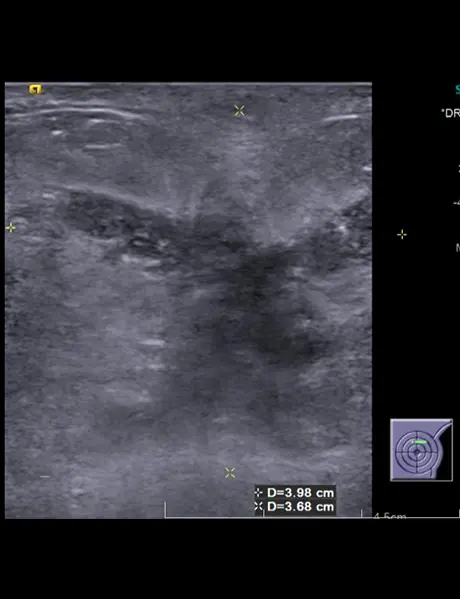

Left breast USG showing mass forming area consisting of multiple thickened dilated ducts extending into the subcutaneous region (straight white arrow). There is parenchymal edema surrounding this area of abnormality.

Multiple enlarged lymph nodes with thickened cortices and loss of fatty hilum in left axilla .